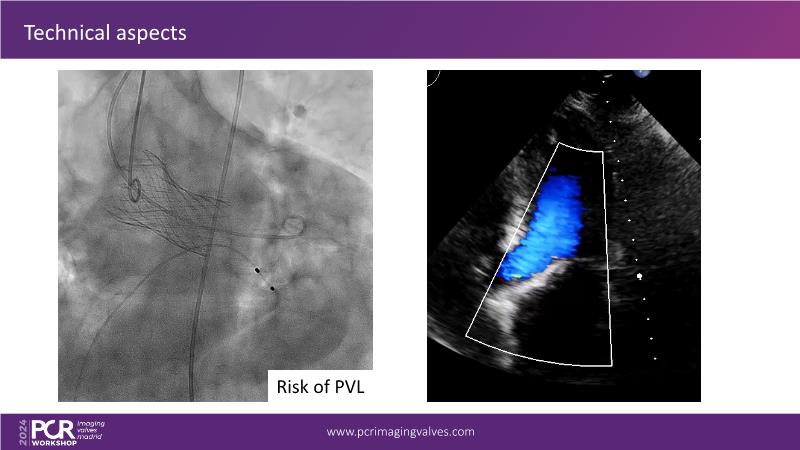

Explore cutting-edge transcatheter valve interventions for mitral and aortic valve disorders, including valve-in-valve procedures and management strategies for paravalvular leakages, and learn about diagnosing and treating mitral annular calcification and transcatheter options in infective endocarditis.

- To get tips and tricks for guidance of transcatheter intervention